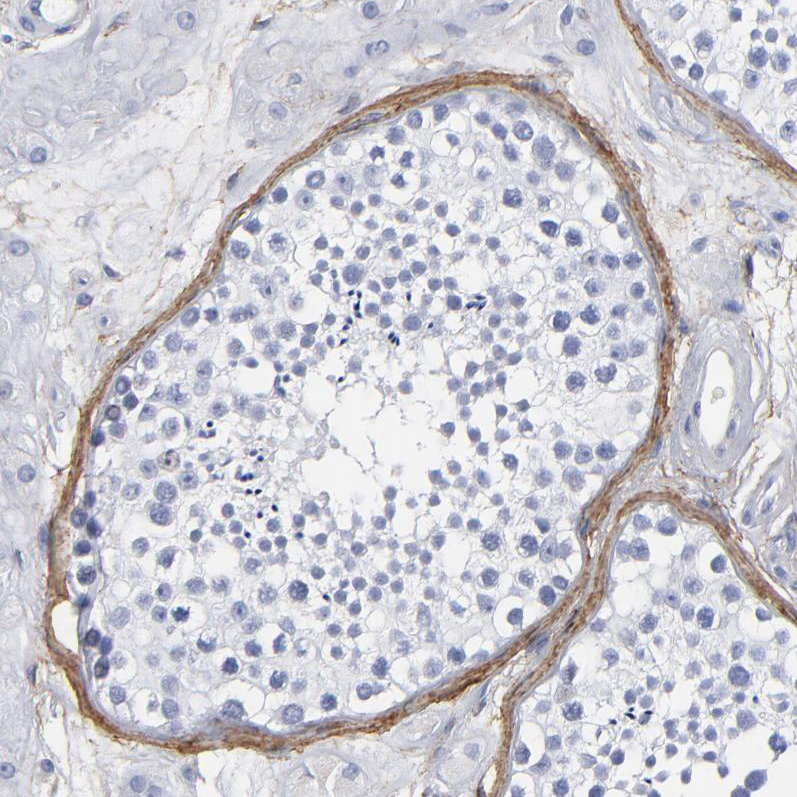

Immunohistochemical staining of human prostate shows strong membranous positivity in smooth muscle cells.